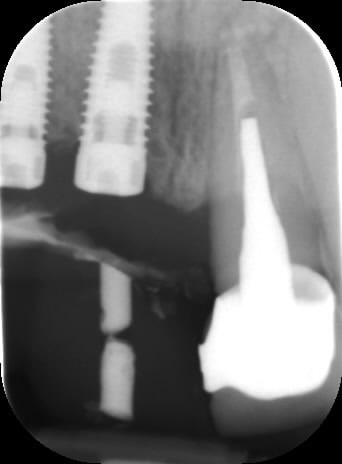

le montage guide RX laisse supposer un manque d'un mm en 12 et ok en 11. Surcomble en cj pour en éliminer au cas où avant les empreintes

Bon ben j'ai implanté avant d'avoir refait la 21. Du coup j'ai mésialé la pose de 11 pour compenser la distalisation de 21.

Au final je n'ai pas fait de greffe osseuse... et j'ai réalisé une technique de rouleau sur 11-12 mais je reste un peu court à mon goût.

J'ai mis en place des transitoires sur 11-12-21 pour temporiser 3 mois pour voir la maturation des tissus mous.

Je réaliserai dans un second temps des piliers procera.

La vraie difficulté a été de retrouver le milieu incisif pour déterminer la position des implants.